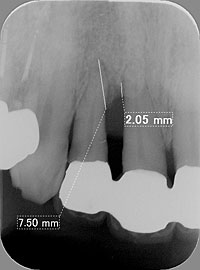

天然歯の歯周組織の骨を回復させ、隣在歯にインプラントを埋入した症例

写真にある変色歯は、歯根破折及び虫歯で歯質が感染崩壊しており、 歯周外科にて確定診断を行い、抜歯しております。

術前 エムドゲイン適応 術後